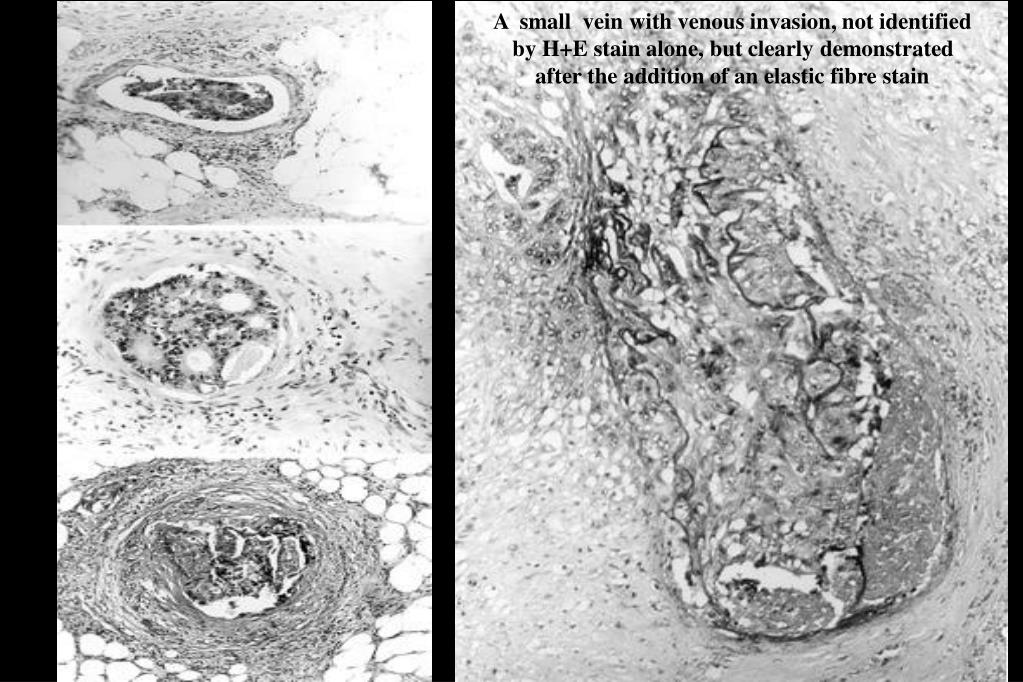

9. A small vein with venous invasion, not identified by H+E stain alone, but clearly demonstrated after the addition of an elastic fibre stain

10. Conclusions from a study of venous invasion instage IV colorectal adenocarcinoma A Sternberg, M Amar, R Alfici and G Groisman Journal of Clinical Pathology 2002;55:17-21 The addition of an elastic fibre stain enables the identification of venous invasion in a large proportion of colorectal carcinomas that are falsely negative on haematoxylin and eosin alone It is probable that only minimal venous invasion is needed to seed clinically important distant metastases Both extramural and intramural venous invasion may seed clinically important haematogenous metastases